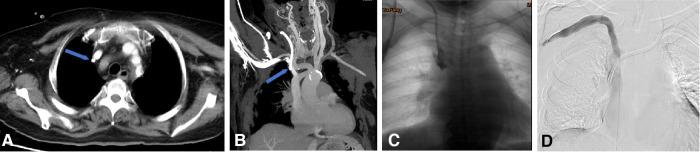

The aim of this study was to evaluate the causes of the dysfunctional tunneled cuffed catheters (TCCs) using multi-spiral computed tomography venography (MSCTV), and to analyze the outcomes of endovascular salvage techniques.

MSCTV showed a range of abnormalities in the hemodialysis (HD) patients, including central venous occlusion ( = 4), fibrin sheath formation ( = 3), malposition of the catheter tips ( = 4), central venous perforation ( = 1), thrombus formation ( = 12), regular catheter exchange without determined lesions ( = 3). Interventional catheter salvage procedures were performed, such as catheter exchange, balloon disruption of a fibrin sheath, angioplasty for central vein stenosis, and stent deployment. The technical success rate for catheter insertions was 100%, and no procedure-related severe complications were observed. The 30-day catheter patency for all assessable catheters was 85.2%.

MSCTV显示血液透析(HD)患者存在一系列异常情况,包括中心静脉闭塞(=4例)、纤维蛋白鞘形成(=3例)、导管尖端位置异常(=4例)、中心静脉穿孔(=1例)、血栓形成(=12例)、无明确病变的常规导管更换(=3例)。实施了介入性导管挽救程序,如导管更换、纤维蛋白鞘球囊破坏、中心静脉狭窄血管成形术和支架置入术。导管插入的技术成功率为100%,未观察到与操作相关的严重并发症。所有可评估导管的30天导管通畅率为85.2%。